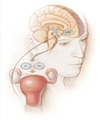

Amenorreia

Compartimento IV?

Hipotálamo.

GO: Amenorreia, SUA e infertilidade

Amenorreia

Compartimento III?

Hipófise.

GO: Amenorreia, SUA e infertilidade

Amenorreia

Compartimento II?

Ovário.

GO: Amenorreia, SUA e infertilidade

Amenorreias

Compartimento I?

Útero e vagina.